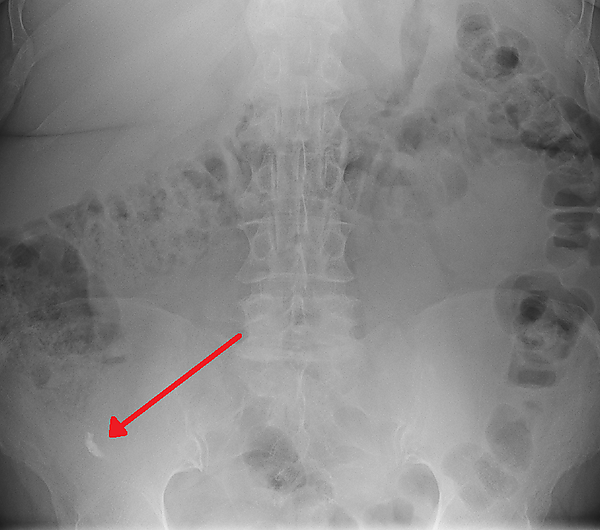

Копролитами (каловыми камнями) также называются одиночные или множественные конкременты шаровидной или овальной формы, возникшие в толстой кишке при продолжительных запорах, аномалиях развития толстой кишки (к примеру, при мегаколоне) вследствие уплотнения каловых масс. Диаметр может достигать 10-15 см, нередко пропитаны неорганическими солями. Также встречаются энтеролиты, возникающие в тонкой кишке, разрастаясь вокруг желчного камня, остатков пищи, волос, медикаментозных средств. У пациентов могут вызывать боль, чувство тяжести в животе, изъязвления, пролежни, папилломатозы, обтурационную кишечную непроходимость, перфорацию стенки, кишечные кровотечения. Удаление — стимуляцией естественного пути выхода либо хирургическое[1]. Копролиты в червеобразном отростке могут быть причиной аппендицита[2].